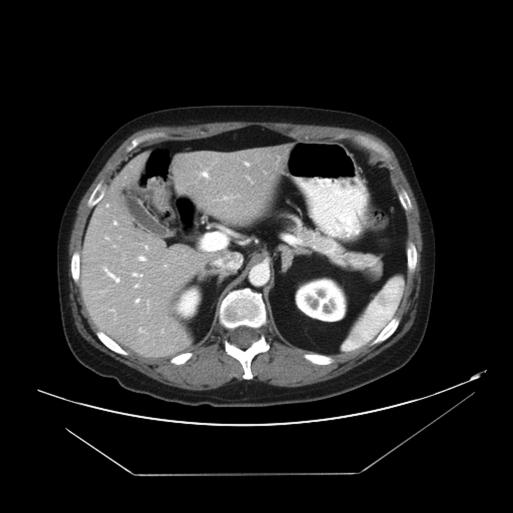

Select patients with ACTH-dependent Cushing's syndrome, such as patients with persistent Cushing's disease after failed hypophysectomy or patients with ectopic ACTH production, may require bilateral adrenalectomy. Laparoscopic bilateral adrenalectomy has been described, offering definitive treatment with reduced morbidity compared with open techniques. We report on the performance of synchronous bilateral adrenalectomy treated using the da Vinci robot (Intuitive Surgical, Sunnyvale, CA). To our knowledge, the usage of this minimally invasive approach for this operation has yet to be reported in literature. The details of the case and a brief review of the literature are described herein.

选择患有促肾上腺皮质激素(ACTH)依赖性库欣综合征的患者,如垂体切除术后仍患有库欣病的患者或产生异位ACTH的患者,可能需要进行双侧肾上腺切除术。腹腔镜双侧肾上腺切除术已被描述,与开放手术相比,它能提供确定性治疗且发病率更低。我们报告了使用达芬奇机器人(直观外科公司,加利福尼亚州森尼韦尔市)进行同步双侧肾上腺切除术的情况。据我们所知,这种微创手术方法在该手术中的应用尚未见文献报道。本文描述了该病例的详细情况并对文献进行了简要回顾。